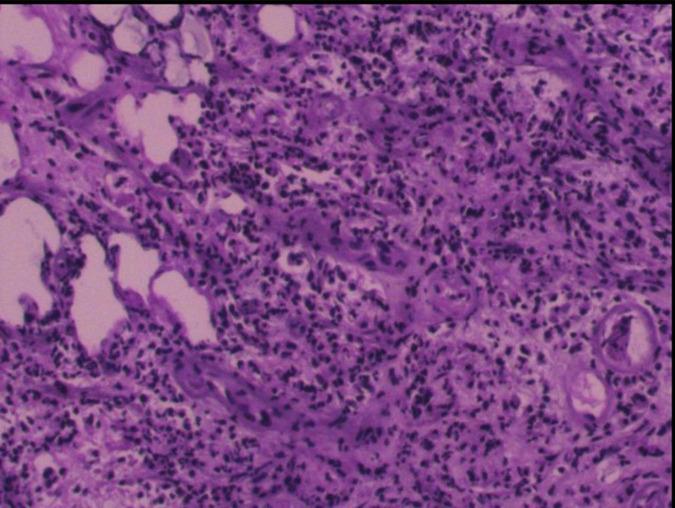

CASE PRESENTATION

A 68-year-old male patient was admitted to our institution presenting with bilateral hearing loss complicated with continuing headaches without obvious cause. Laboratory tests indicated positive treponema pallidum. Conventional MRI showed nodules closely related to the adjacent meninges in bilateral temporal lobes. The patient underwent surgical resection of the nodule in the right temporal lobe due to the mass effect and the final pathological diagnosis revealed cerebral syphilitic gumma.